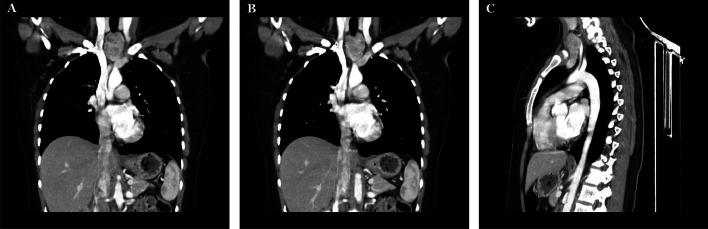

Ectopic thyroid tissue is an uncommon migratory anomaly of the thyroid, occurring in 1 in 100,000 to 300,000 individuals, with a greater prevalence in females. Although lingual ectopic thyroid represents 90% of cases, extralingual sites, such as the mediastinum, are less common. Despite being frequently asymptomatic, it can present with dysphagia and dyspnea because of mass impact. A 27-year-old Saudi woman with progressive dysphagia and intermittent. Imaging demonstrates a well-defined retrosternal mass distinct from the native thyroid gland. Fine-needle aspiration verified benign multinodular thyroid tissue. A successful surgical excision was conducted by a low cervical approach without the need for sternotomy. Histopathology confirmed benign ectopic thyroid tissue, and the patient had an uncomplicated recovery with normal thyroid function postoperatively. This case highlights the significance of considering Ectopic thyroid tissue in the differential diagnosis of anterior neck masses causing dysphagia and contributes to the limited literature on ectopic thyroid presentations.

异位甲状腺组织是一种罕见的甲状腺迁移异常,在10万至30万人中出现1例,女性患病率更高。虽然舌部异位甲状腺占病例的90%,但舌外部位,如纵隔,较为少见。尽管通常无症状,但由于肿块的影响,可出现吞咽困难和呼吸困难。一名27岁的沙特女性,有进行性吞咽困难和间歇性症状。影像学显示胸骨后有一个边界清晰的肿块,与正常甲状腺不同。细针穿刺证实为良性多结节甲状腺组织。通过低位颈部入路成功进行了手术切除,无需胸骨切开术。组织病理学证实为良性异位甲状腺组织,患者术后恢复顺利,甲状腺功能正常。该病例突出了在导致吞咽困难的前颈部肿块鉴别诊断中考虑异位甲状腺组织的重要性,并为关于异位甲状腺表现的有限文献做出了贡献。